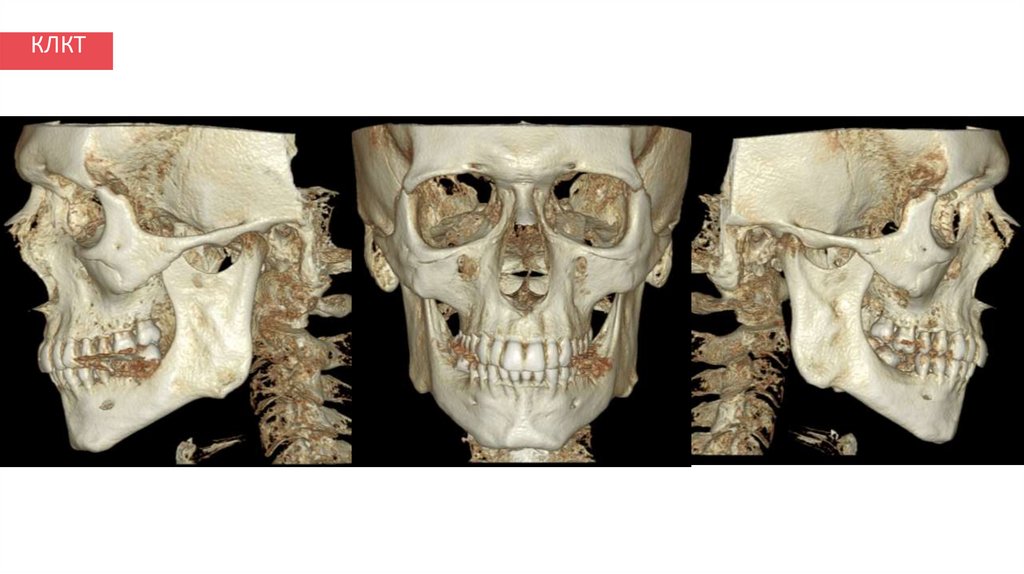

КЛКТ

12. КЛКТ